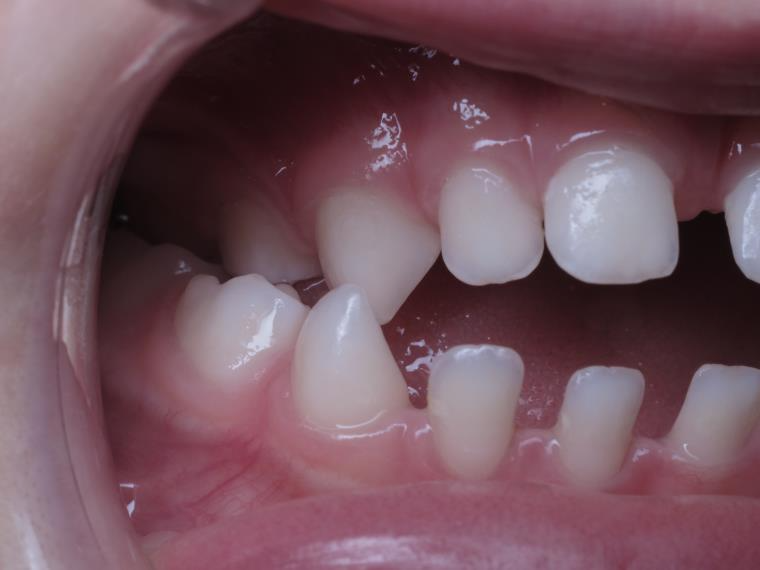

18 béance inversé droit 4 ans

inversion des dents postérieur et espace entre l'arcade du haut et du bas (béance)

bilan de début et en cours de traitement